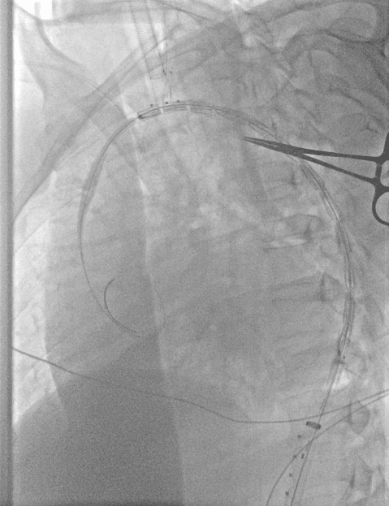

1、穿刺患者左肱动脉与右股动脉,并在左肱动脉置入5F的穿刺鞘后,导入软导丝,从右股动脉导入7F长鞘至降主动脉,交换超硬导丝与分支导丝并导入造影导管进行造影;

动脉长鞘怎么置入【弓部重建直通车】真腔难觅,另辟蹊径|潍坊市人民医院血管外科运用Castor®支架结合长鞘建立导丝通路治疗主动脉夹层两例_https://www.jmylbn.com_新闻资讯_第8张

与长鞘并行导入造影导管

动脉长鞘怎么置入【弓部重建直通车】真腔难觅,另辟蹊径|潍坊市人民医院血管外科运用Castor®支架结合长鞘建立导丝通路治疗主动脉夹层两例_https://www.jmylbn.com_新闻资讯_第9张

术前造影